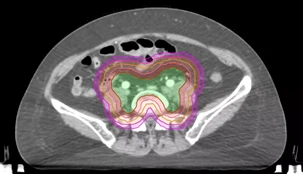

上图红色区域为脚本根据处方剂量自动使用布尔运算生成的PTV-(PGTVnd+5mm)结构(PTV-蓝色,PGTV-绿色)

优化过程中脚本会将靶区和危及器官的剂量与临床协议模板进行比较,没有达到要求的靶区和器官会自动更改优化参数,重新开始优化,直到全部满足预设条件。随后开始最终剂量计算,并将计算结果与临床协议模板进行比较,满足的话就结束运算,不满足则调整优化参数重新回到计划优化部分。通过以上逻辑,就可以把相对简单的计划做到满足临床使用的标准,而且能够节省大量时间。下图为最终运算结果:

自动计划脚本的运行结果满足了所有靶区和危及器官的临床目标,图示计划从打开患者病例到得到最终结果,整个流程耗时8分钟左右(操作脚本1分钟,脚本自动运行7分钟)。ESAPI的C#语言使用了MVVM(Model-View-ViewModel)模式,界面跟代码实现了解耦,想修改界面、增减功能都不需要大动底层的逻辑代码,对临床使用者非常友好,因为我们在开发的过程中会不断有新的想法、需求,需要不断的修改。